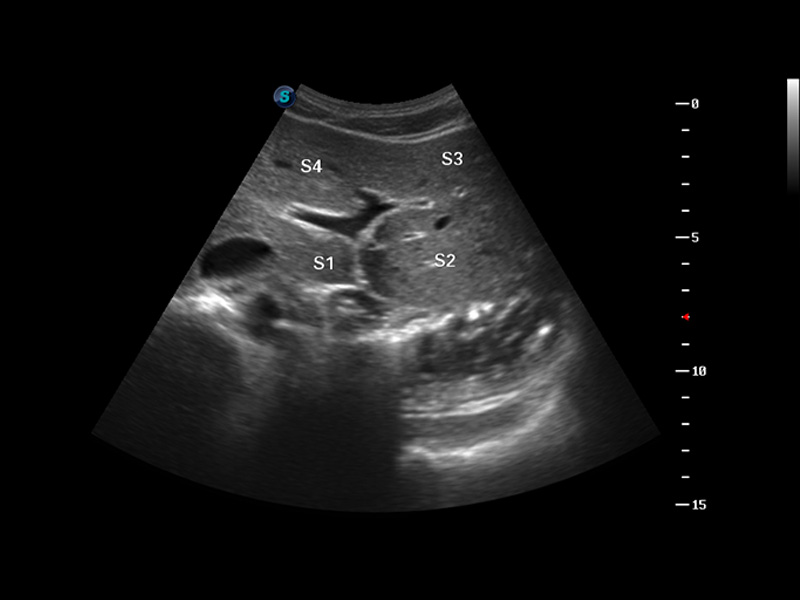

S8 EXP便携式彩色多普勒超声诊断仪是银河优越会研发的高端全身应用型便携彩超。高通道的VIS平台融合可视化(Visual)、智能化(Intelligent)和人性化(Smart)的特点,配以银河优越会自主研发生产的探头大家族,使您能够快速、准确的获得病人信息,提高工作效率的同时减轻疲劳。

μ-Scan微米成像

谐波成像